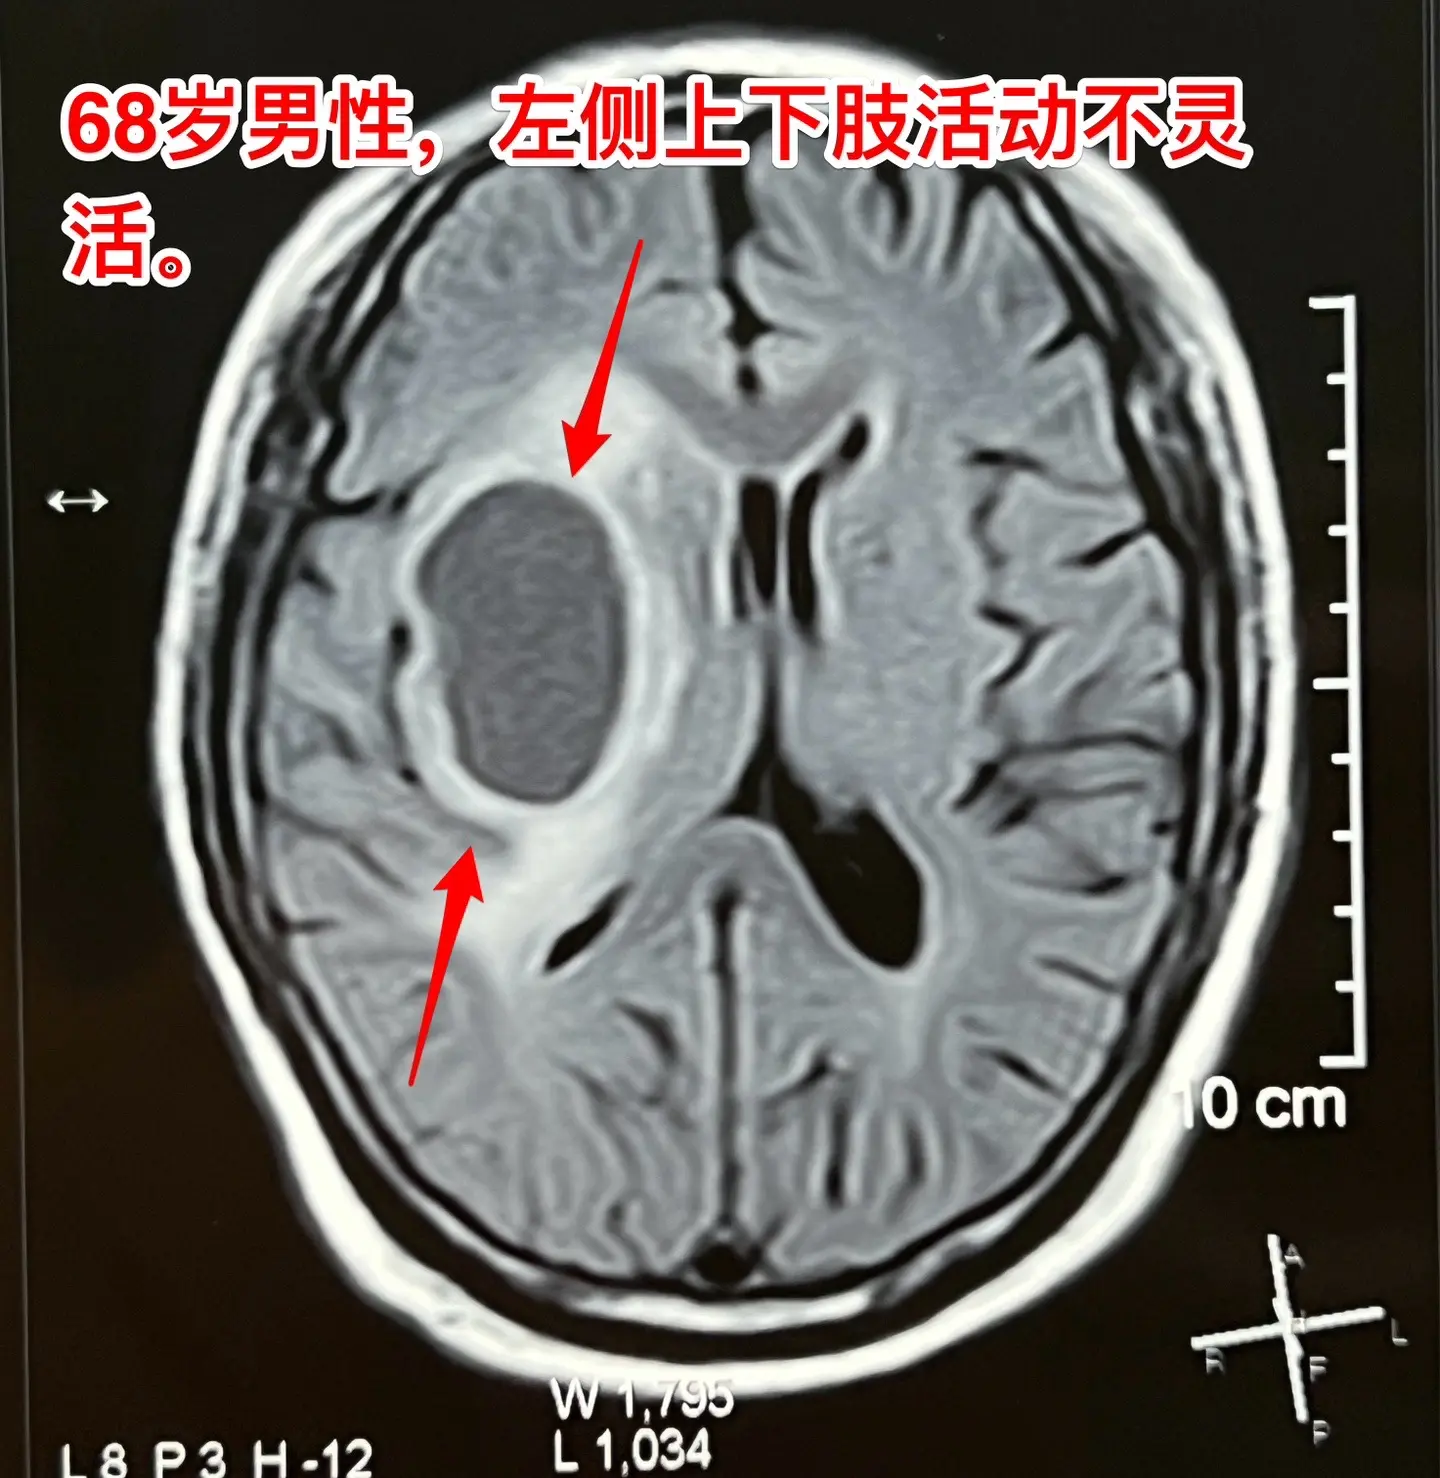

老人擀饺子皮的质量下降了,原因是什么?68岁的唐山市老人,擅长擀饺子皮、包饺子,平时擀出的饺子皮中央稍厚、四周均匀薄。然而近期他擀出的饺子皮形态不规整,厚薄一致,与平时的水准大相径庭,是什么原因呢?而且家人发现他穿鞋系鞋带动作又慢又笨拙!跟平时完全不一样。 病人的女儿在北京当医生。 到医院去检查脑部磁共振就发现脑部长了一个瘤。这个瘤位于左侧颞叶-基底节区,压迫内囊区域,虽然没有造成明显的偏瘫症状,但是也造成了左侧上下肢活动不灵活。 8.16到我这里来住院,8.23作了手术,术中的快速冰冻病理提示高级别神经上皮肿瘤,即胶质瘤的一种。 手术后老人没有出现明显的偏瘫症状。 这样的肿瘤单纯作手术是不够的,还需要作放疗、化疗。